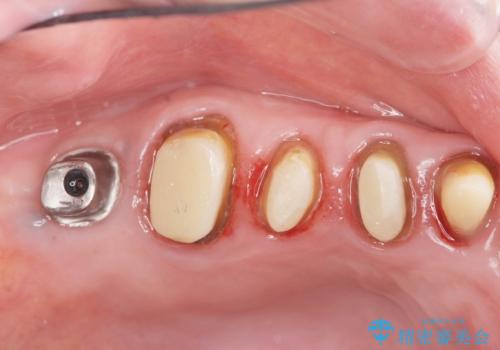

- 色や形、適合の悪いクラウンの再治療を希望され来院されました。

装着されているクラウンを除去し、自然な色調のジルコニアクラウンによる審美生の改善、インプラントを用いた欠損部の機能回復を計画します。

- 88万円(インプラント・チタンカスタムアバットメント・ジルコニアクラウン×4・仮歯×4)費用は治療当時の料金となります